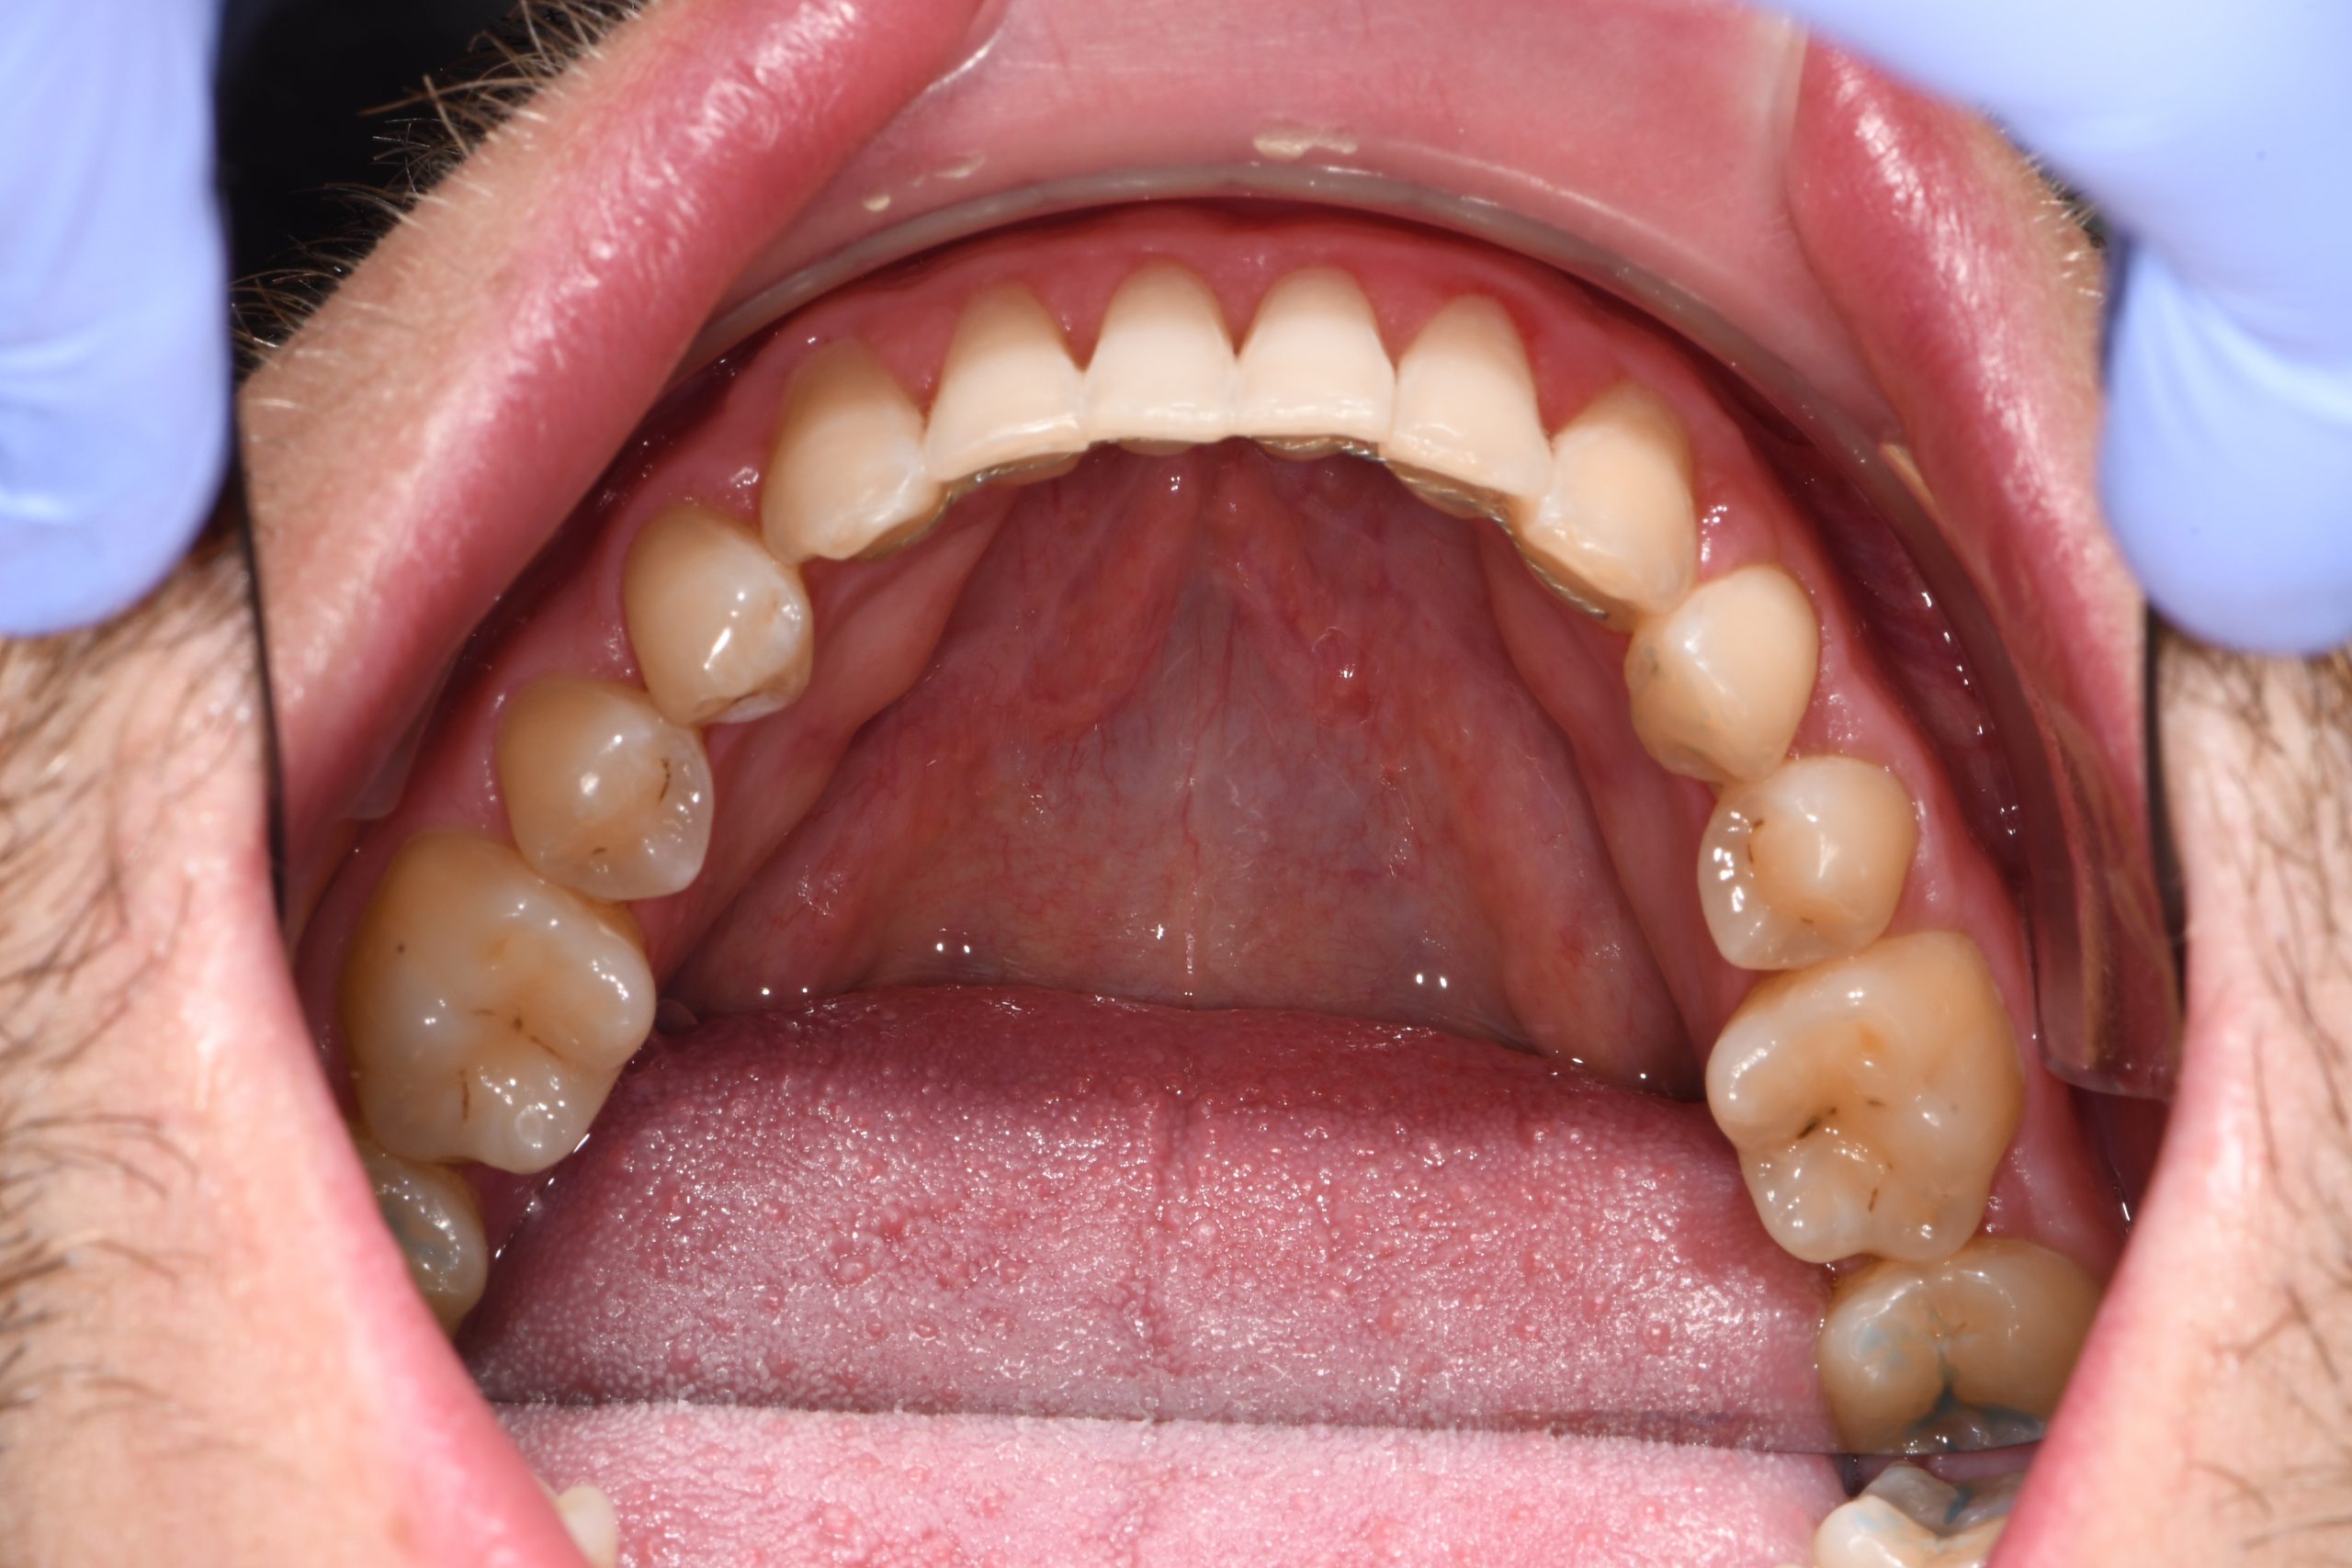

Az elmúlt évekből rengeteg szakmai referenciát tudnánk bemutatni, amelyek különböző fogszabályozási problémákat oldottak meg. Válogatva a több száz esetből, ezen az oldalon olyan képeket, információkat igyekeztünk bemutatni, amelyeknek a segítségével a jövőbeni pácienseinknek azt tudjuk üzenni: A Te fogsorod is lehet gyönyörű!

(Képeket a Pácienseink külön írásos beleegyezésével mutatjuk be!)